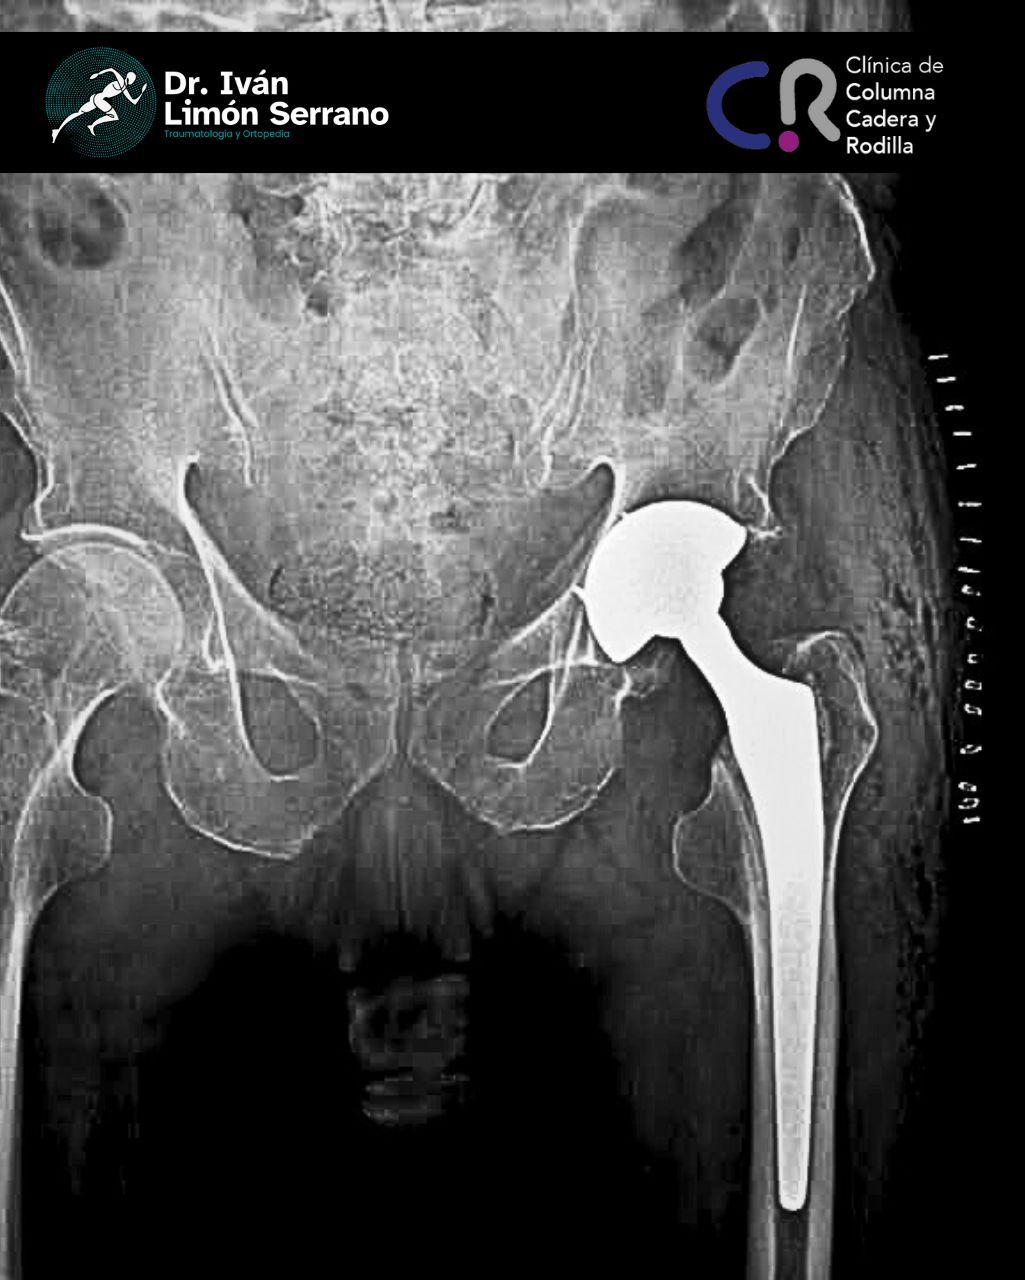

• Prótesis de cadera

Es una enfermedad articular caracterizada por la por degeneración, perdida del cartílago y alteración del hueso subcondral asociado a cambios en tejidos blandos. Se caracteriza por dolor articular, limitación funcional, crepitación y grados variables de inflamación. Factores de riego como sobrepeso, obesidad, debilidad muscular, actividad física pesada traumatismos, edad avanzada, sexo femenino, factores genéticos, trastornos metabólicos y congénito. Actualmente existen tratamientos desde lo no farmacológico control de peso hasta el tratamiento quirúrgico como lo es el reemplazo articular mediante la colocación de prótesis total.